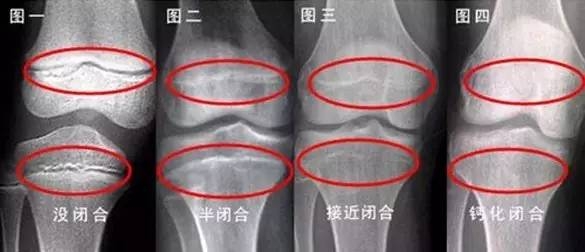

一旦骨龄闭合就无法长高

当他摇着头表示骨龄已经闭合时,家长问:“什么是骨龄,闭合是什么意思?”余绍淼解释,骨龄是国内外公认能精确反映人体成熟度、骨骼生长状况的一个重要指标。根据孩子当前的骨龄,就可以预测出他还可能长多高。骨龄一旦闭合,身高将停止生长。

这意味着,所有能够让孩子长高的方法都必须在骨龄未闭合前进行。“通常,女孩在15岁时骨龄闭合,男孩的骨龄闭合时间则在16岁,因个体差异闭合的时间也有所差别。”余绍淼说。

他们先是被安排做了骨龄检查,片子显示,小张的骨龄已经15岁了,接近骨龄闭合。余绍淼告诉他们,“小张需要抓紧治疗,趁着骨龄还没有完全闭合,还有再长高的空间。经推算,他的遗传身高在170厘米,经过治疗能长到遗传身高。”

余绍淼拿到了明明的片子,“他的骨头间的缝隙已经没有了,我没有办法再让他长高了。”

“会不会弄错了?我的孩子还能长高吧。”“我不会跟您开玩笑的,骨龄已经闭合了。”